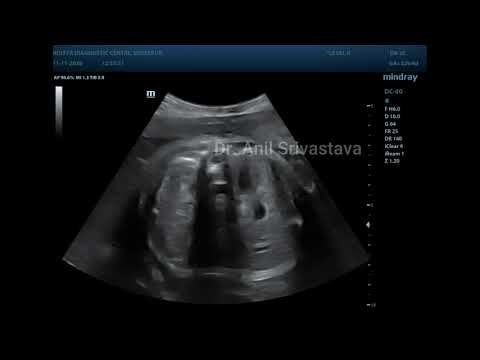

HYDRONEPHROSIS